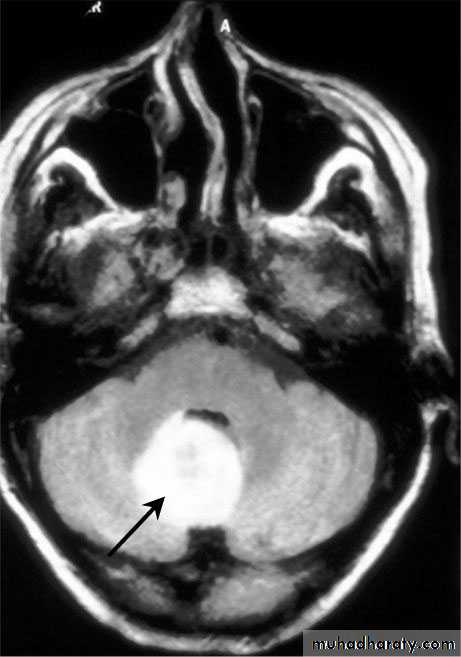

Cerebellar Abscess

• Cerebellar Abscesses.